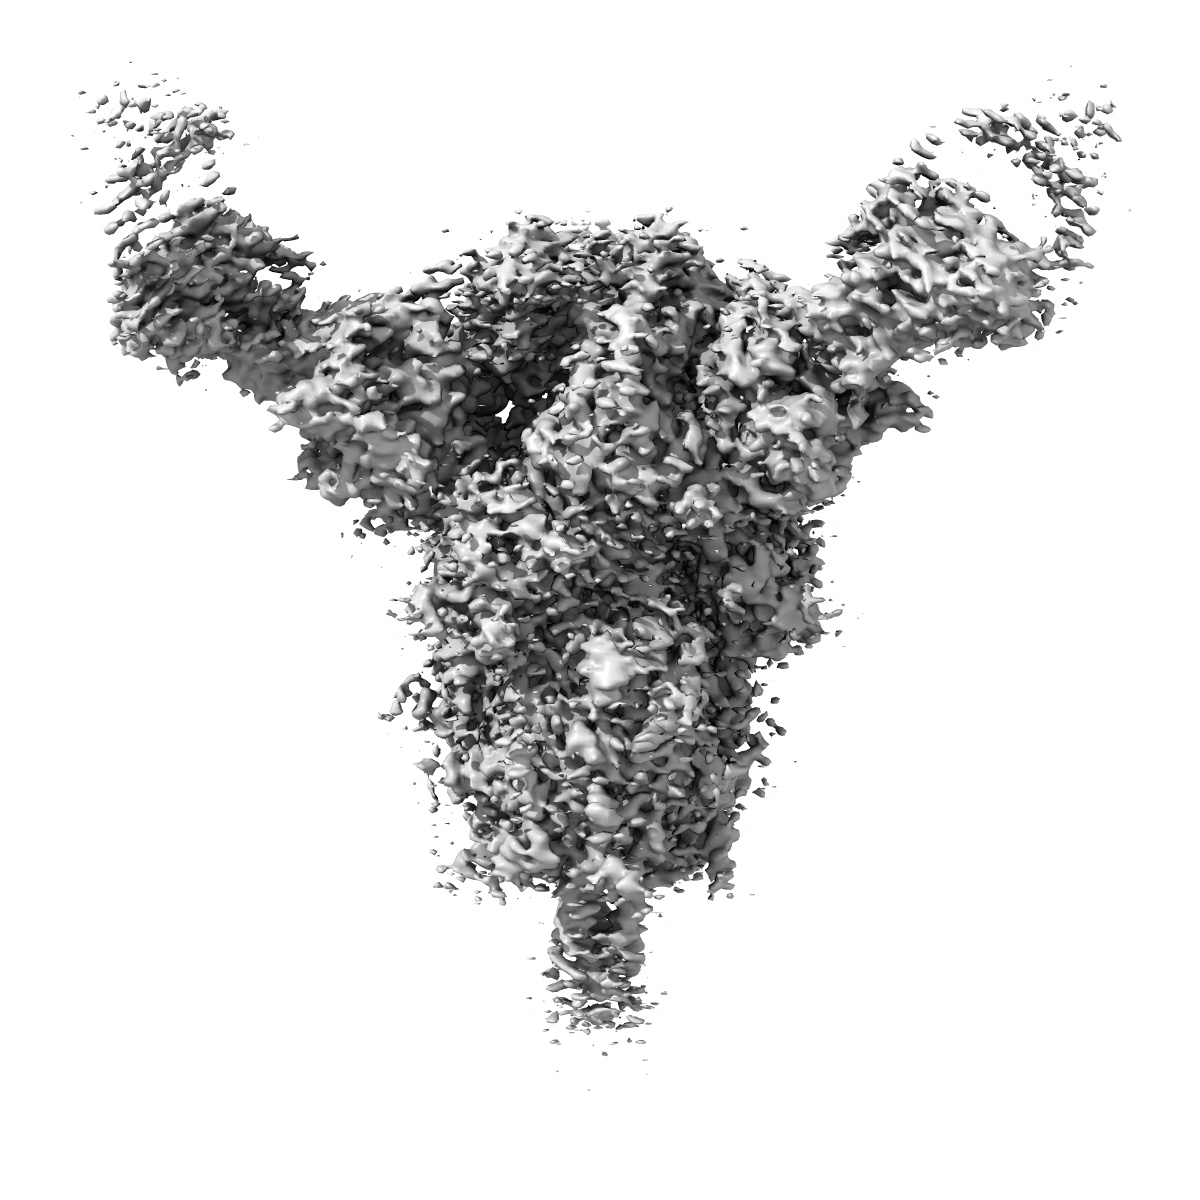

Cryo-EM structure of SARS-CoV-2 spike protein in complex with neutralizing human antibody WRAIR-2008

Single-particle3.23 Å

Sample: SARS-CoV-2 spike protein with WRAIR-2008 Fab

First-generation N-terminal domain supersite public antibodies retain activity against Omicron-derived lineages and protect mice against Omicron BA.5 challenge.